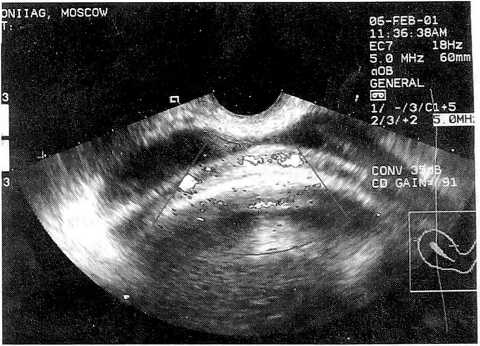

Мы располагаем случаями самопроизвольных родов при равномерной толщине рубца 3-4 мм (рис. 1) с хорошей его васкуляризацией. Кстати, такова толщина и интактного нижнего сегмента матки в конце беременности и в родах. Рубец же, где имеются локальные истончения, независимо от его общей толщины (рис. 2), по нашему мнению, является неполноценным.

Рис. 2. Васкуляризация состоятельного рубца на матке